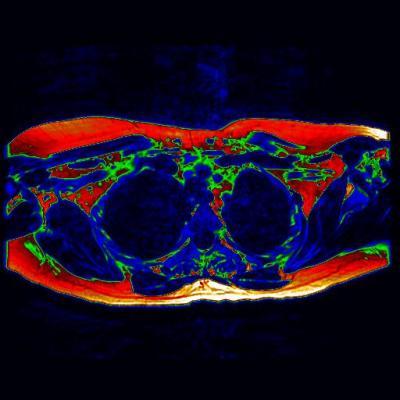

April 18, 2014 — The first MRI (magnetic resonance imaging) scan to show 'brown fat' in a living adult could prove to be an essential step toward a new wave of therapies to aid the fight against diabetes and obesity.